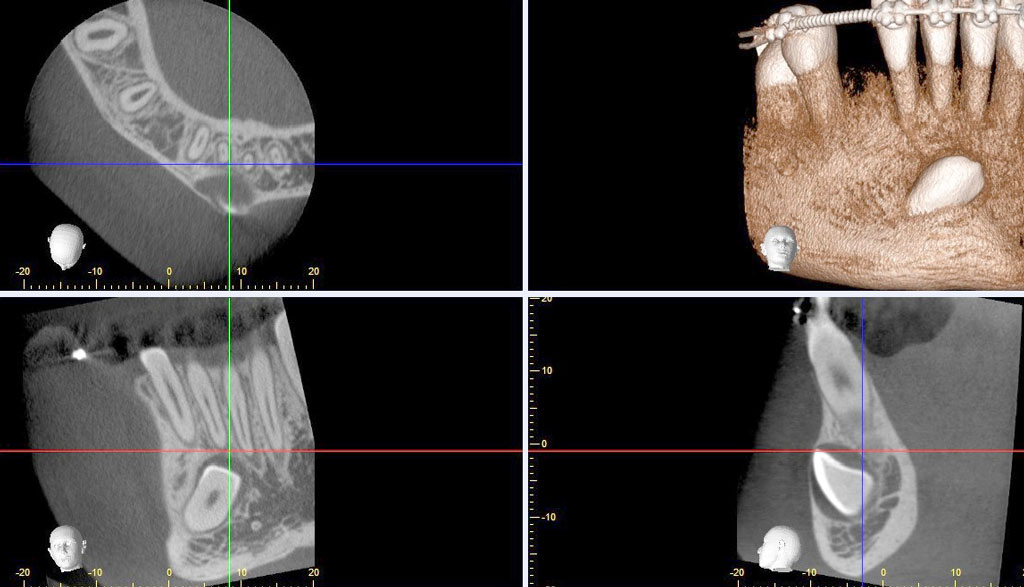

How to read cbct for dental implants Dental News Network

How to read cbct for dental implants Dental News Network Indications Of Cbct In Dentistry dental radiography is a vital part of clinical dentistry and cbct (cone beam computed tomography), a. Cbct may be indicated for: Cbct has applications in nearly all aspects of dentistry, and there have been several. apart from above discussed applications in dentistry, cbct have uses. the developing dentition. indications for cbct. • localization of an unerupted. Indications Of Cbct In Dentistry.